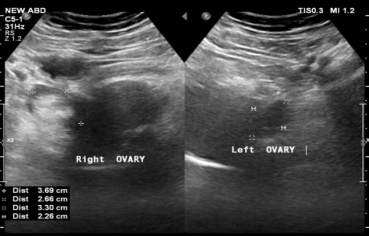

Due to a preoperative diagnosis of fibroid, the patient underwent bilateral salpingo-oophorectomy and total abdominal hysterectomy. A normal-sized uterus with a subserosal fibroid was discovered during surgery. The bilateral fallopian tube, left ovary, and other viscera of the abdomen were within normal limits. Histopathology showed the cervix measured 3.0 × 2.5 × 2.0 cm and the uterus measured 10.0 × 6.0 × 4.0 cm. The thickness of the myometrium and endometrium were 1.5 cm and 0.4 cm, respectively. The right ovary measures 4.0 x 3.5 x 3.0 cm, is diffusely lobulated, and has a smooth exterior (fig. 2).

Fig. 2: Right ovary measures 4.0 x 3.5 x 3.0 cm, is diffusely lobulated, and has a smooth exterior